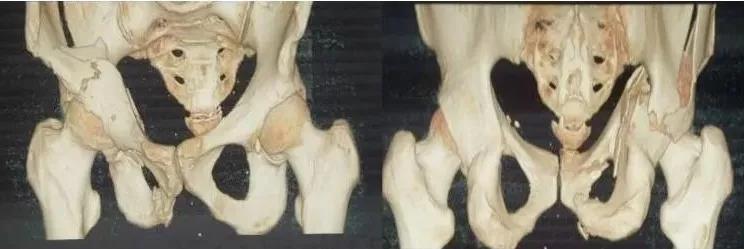

3)髋臼骨折(伤后5-7天)

- 人体最大的负重关节,精确复位可达到关节的最佳匹配,确保正常力学性能;

- 影像学移位程度大,不匹配>2mm--手术;

- 髋关节脱位,髋臼后壁骨折并股骨头骨折,复位后关节仍然不稳,或关节腔有游离骨块--手术。

并发症:异位骨化18-90%;股骨头坏死3-9%